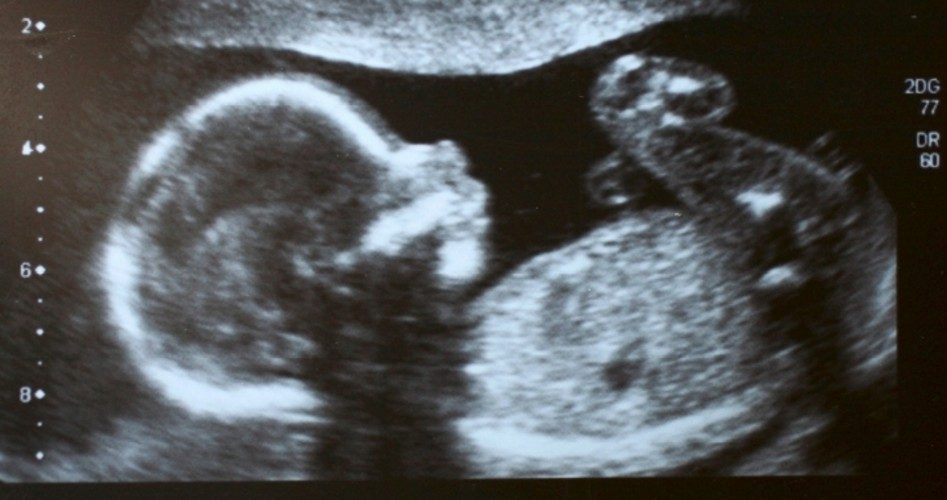

The bill also requires anyone seeking an abortion to have an ultrasound before the procedure, and bars physicians from performing abortions if they become aware that the abortion is “motivated by sex, race, or disability diagnosis of the unborn child.”